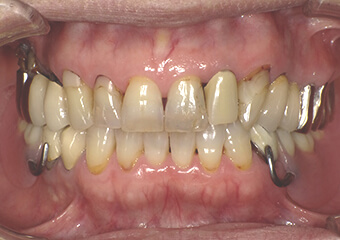

一般的な設計の入れ歯(保険適用)

金属のバネのない入れ歯(正面)

金属のバネを使用しない“ノンクラスプデンチャー”の製作も可能です。保険適用の義歯と比較して外観の回復の点で大きなメリットがあります。